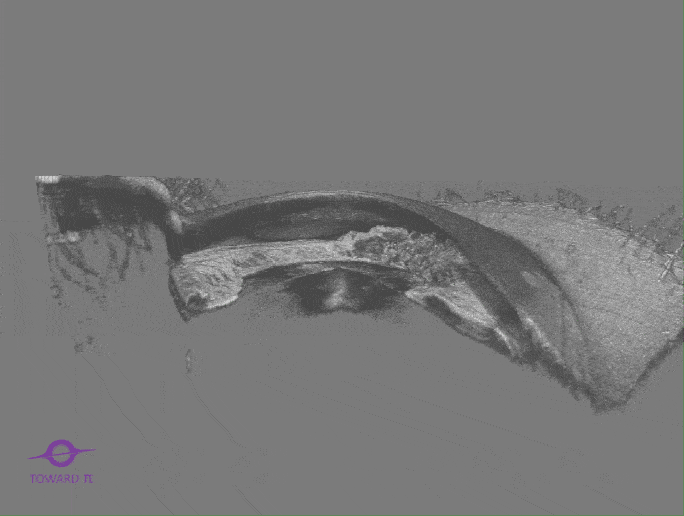

BMizar (BM-400K) es el OCT más potente de la industria con una fuente de barrido de 400 kHz. Su excepcional diseño óptico eleva la experiencia de la Angiografía OCT a un nivel sin precedentes. Con imágenes de alta definición de la retina, la coroides y el segmento anterior, cubre sin esfuerzo un área increíblemente grande en un solo escaneo (logrando un OCTA de 24 mm de ancho en solo 7-15 segundos).

Esta tecnología revolucionaria es un cambio de juego para las prácticas clínicas, particularmente en el diagnóstico y tratamiento de enfermedades como DR, RVO, RAO y más. Además, el BMizar ofrece un amplio rango de adaptación dióptrica, lo que hace factible realizar todo tipo de escaneos OCT/OCTA en pequeños animales como conejos, cobayas e incluso ratones sin necesidad de lentes adicionales. Es verdaderamente un equipo de ensueño para cualquier usuario de OCT.